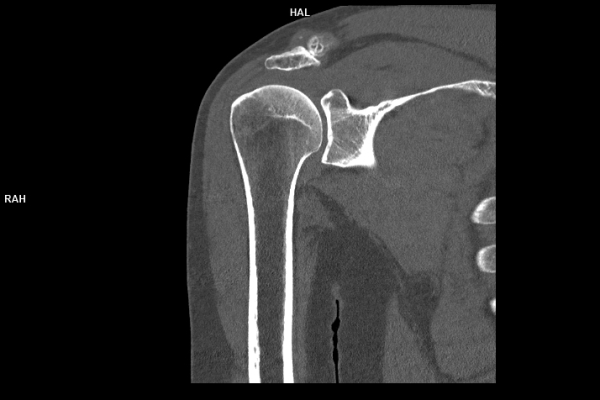

CT Untersuchung Bild

Was ist der Unterschied zwischen einer MRT- und einer CT-Untersuchung?

Die MRT (Magnetresonanztomographie) arbeitet mit Magnetfeldern und Radiowellen und eignet sich besonders für Untersuchungen der Weichteile wie Gehirn, Muskeln oder Gelenke. Die CT (Computertomographie) nutzt Röntgenstrahlen und liefert schnelle, hochauflösende Bilder, insbesondere für Knochen, Lunge oder innere Organe. Die Wahl der jeweiligen Untersuchung richtet sich an das individuelle Krankheitsbild und wird bei der Überweisung festgelegt.